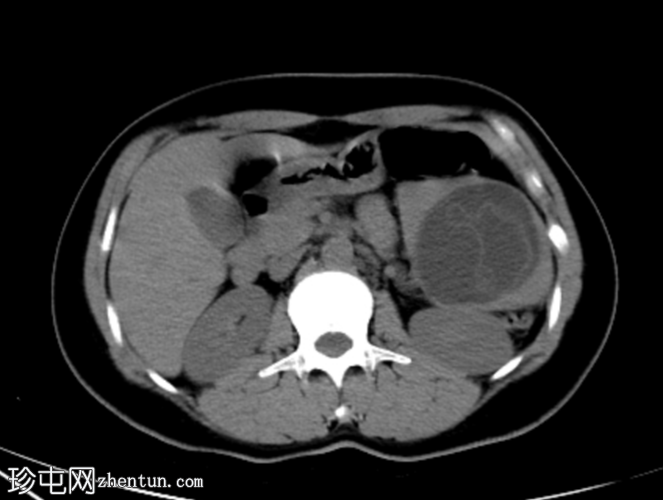

平扫

CT

再次显示肝脾多发性囊肿,脾囊肿内层脱离。

肝脾包虫囊肿的典型

影像

学表现。